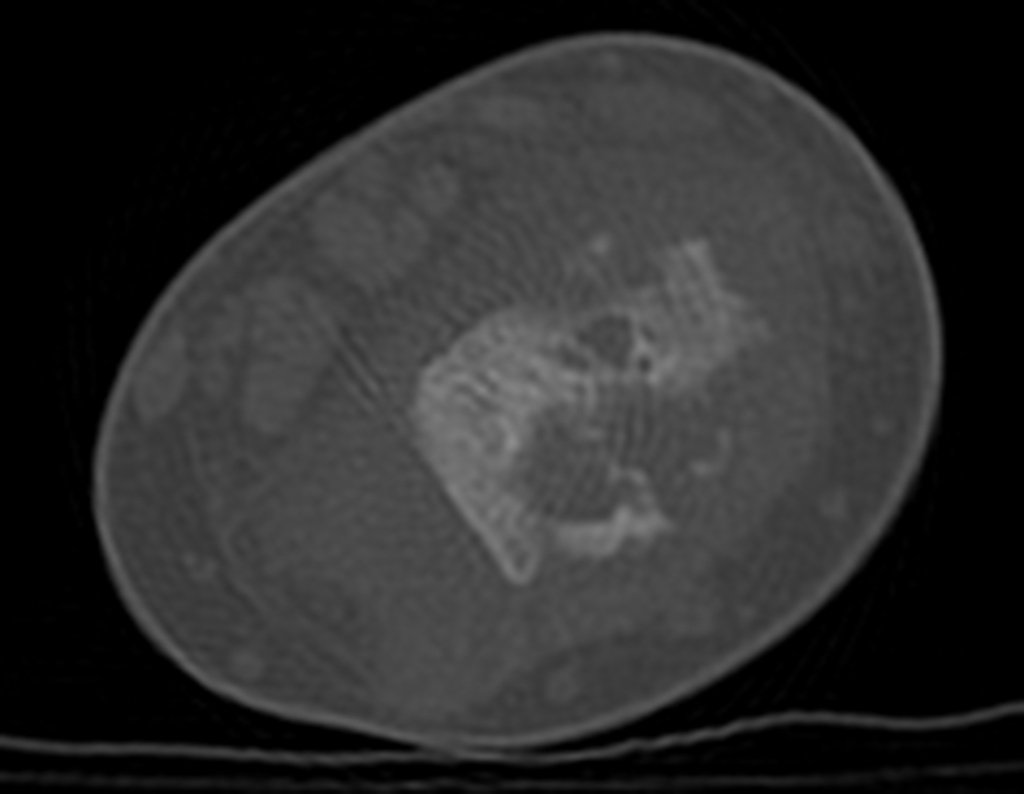

Después de una semana, el 14/08/2015, se retiró la férula y se encontró edema residual en la muñeca y dolor local. La semana siguiente, el 17/08/2015, fue evaluado por otro ortopedista quien repitió las radiografías y diagnosticó un quiste en el radio y una pequeña fractura arriba, figuras 1 a 5.

El domingo 20/09/2015, después de un día de mucha actividad física, caminar, nadar, se presentó aumento de edema y dolor en la muñeca derecha. Al día siguiente se realizaron nuevas radiografías de muñeca, que identificaron la evolución de la lesión, figuras 6 y 7.

Em 30 de maio de 2016, após seis meses de tratamento com Vimblastina EV, Mercaptopurina e Meticorten (50 mg) o paciente retorna para avaliação. Neste período teve um episódio de dor e edema do punho em Janeiro de 2016, cujas radiografias são apresentadas nas figuras 142 e 143. Manteve o punho imobilizado e reavaliou-se em 11-04-2016, figuras 144 e 145.

En la misma fecha, 23/05/2016, se le realizó un examen de resonancia magnética, como se muestra en las figuras 159 a 172.